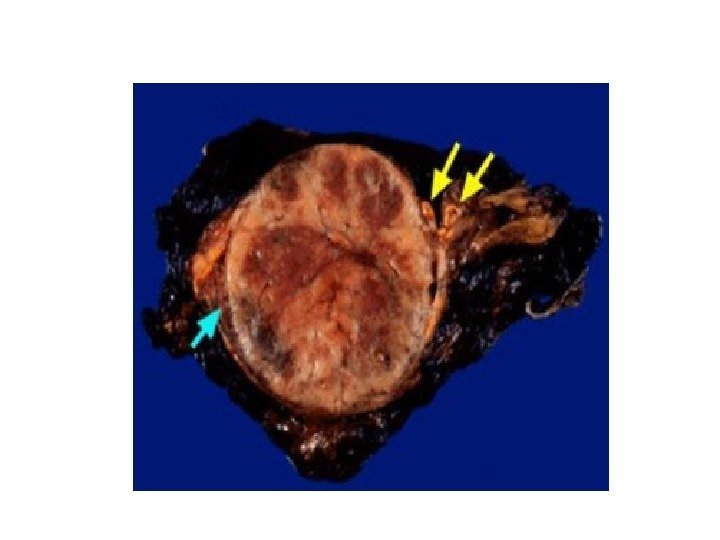

• В 10% случаев при феохромоцитоме компьютерная томография выявляет двустороннее поражение надпочечников. • Билатеральная феохромоцитома часто проявляется как незначительное увеличение надпочечников, с заметным повышением их васкуляризации. • Необходимо помнить, что феохромоцитома может иметь и вненадпочечниковую локализацию, располагаясь в паракавальных симпатических ганглиях, симпатических ганглиях средостения, ганглиях стенки мочевого пузыря.

• В 10% случаев при феохромоцитоме компьютерная томография выявляет двустороннее поражение надпочечников. • Билатеральная феохромоцитома часто проявляется как незначительное увеличение надпочечников, с заметным повышением их васкуляризации. • Необходимо помнить, что феохромоцитома может иметь и вненадпочечниковую локализацию, располагаясь в паракавальных симпатических ганглиях, симпатических ганглиях средостения, ганглиях стенки мочевого пузыря.

ФЕОХРОМОЦИТОМА

ФЕОХРОМОЦИТОМА